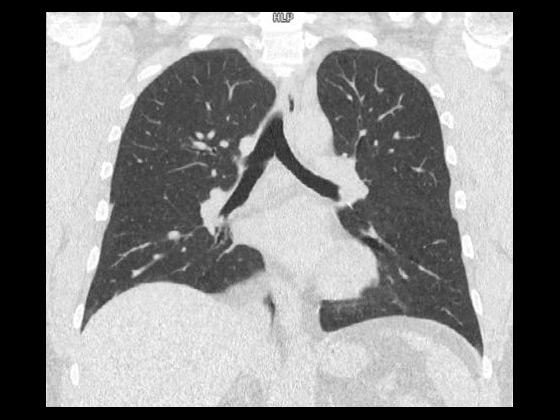

With a mobile lung cancer screening program, you can bring the low-dose CT exam that at-risk patients need closer to where they live. With a short set-up, our self-contained Mobile Lung Screening Solution with a SOMATOM go.Up CT scanner offers the high image quality, ease of use, and flexibility you need to create a lung screening program that meets the real-life needs of your community.